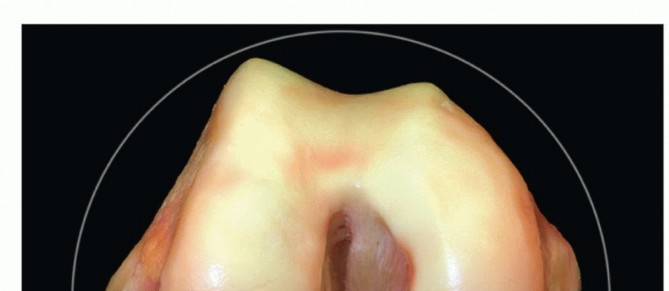

DEFINITION Trochlear dysplasia is a pathologic condition occurring in approximately 3% of the population but …